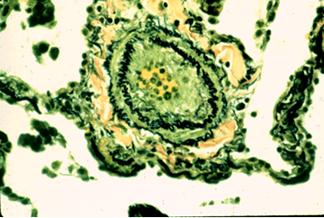

Aspect histologic arteriolar de HTP primara Leziuni plexiforme intr-un caz de HTP primara